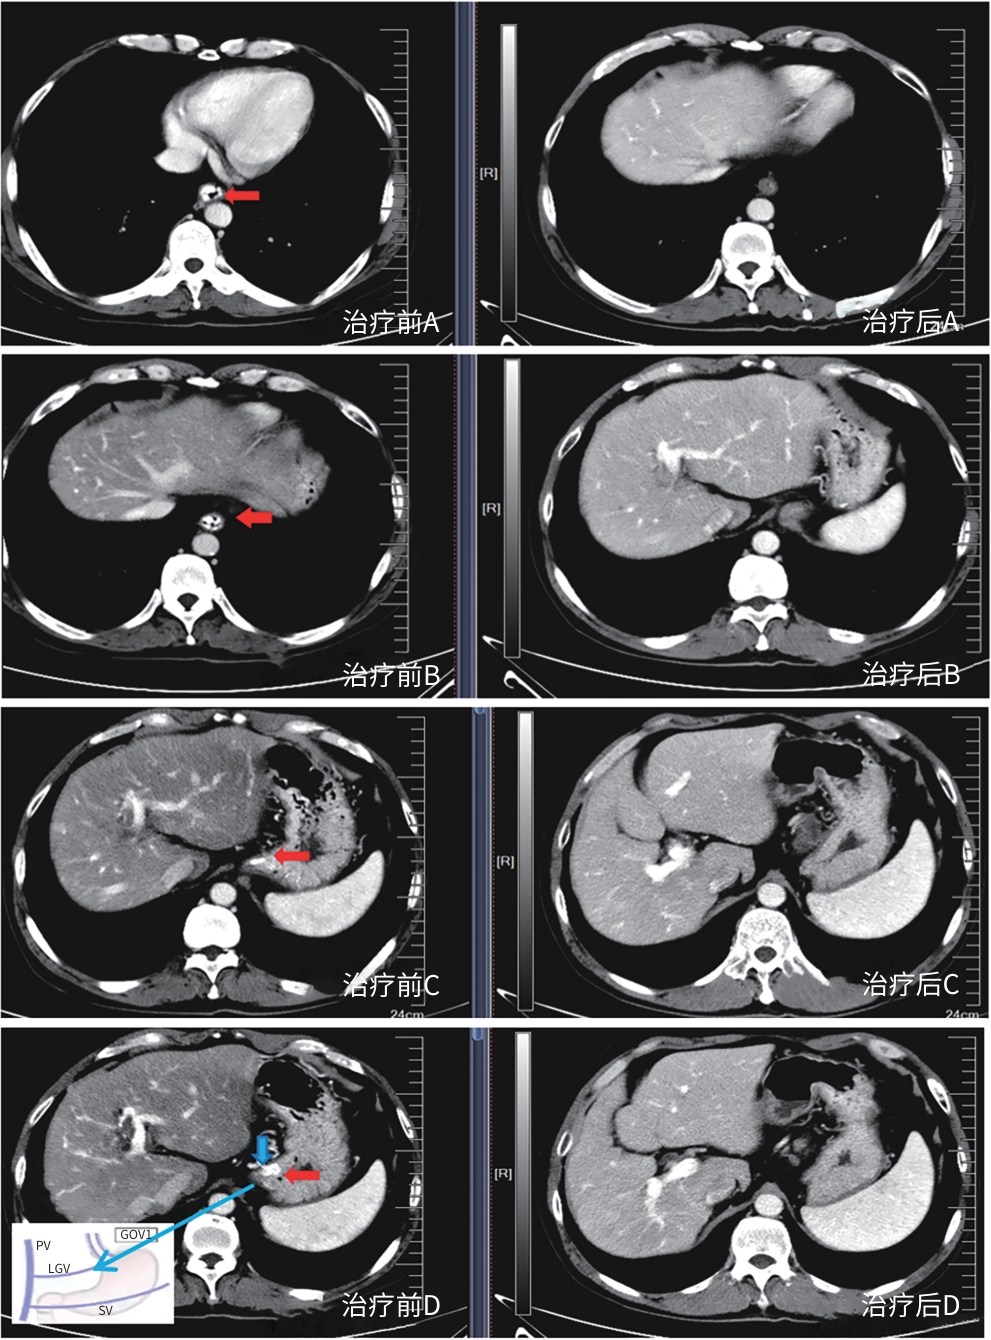

Safety and efficacy of puncture cyanoacrylate selective seal under endoscopic ultrasound versus traditional endoscopy in treatment of gastroesophageal varices: A randomized controlled trial

Jiali MA, Lingling HE, Hongshan WEI, Ping LI, Xiuxia LIANG

2025, 41(6): 1113-1119. DOI: 10.12449/JCH250617

Abstract(1041) HTML (180) PDF (1855KB)(64)

Abstract:

Objective  To investigate the safety and efficacy of puncture cyanoacrylate selective seal (PCSS) under endoscopic ultrasound in the treatment of gastroesophageal varices (GOV).  Methods  A total of 100 patients with liver cirrhosis who underwent endoscopic therapy for the secondary prevention of GOV bleeding in Beijing Ditan Hospital, Capital Medical University, from March 1 to December 31, 2023 were enrolled and randomly divided into PCSS group and traditional endoscopy group. The patients were followed up for 6 months after surgery, and the two groups were compared in terms of clinical outcome and complications. The primary outcome measure was the rate of alleviation or disappearance of GOV, and the secondary outcome measure was variceal rebleeding and death. The independent-samples t test was used for comparison of normally distributed or approximately normally distributed quantitative data between two groups, and the Wilcoxon non-parametric test was used for comparison of non-normally distributed quantitative data between two groups; the chi-square test or the Fisher’s exact test was used for comparison of qualitative data between two groups.  Results  There were 50 patients in the PCSS group, among whom 1 patient was lost to follow-up, and there were 50 patients in the traditional endoscopy group, among whom 3 patients were lost to follow-up. There were no significant differences between the two groups in baseline data such as age, sex, Child-Pugh class, varices grade, and GOV typing (all P>0.05). Compared with the traditional endoscopy group, the PCSS group had significantly better results of the number of endoscopic treatment sessions (t=-15.671, P=0.001), the total amount of tissue adhesive used (t=-2.830, P=0.006), and the rate of alleviation or eradication of varices sclerosis (χ2=7.078, P=0.029). Both groups had low rates of postoperative rebleeding, adverse reactions, and complications, and there were no significant differences between the two groups (all P>0.05).  Conclusion  Compared with traditional endoscopy, PCSS can significantly enhance treatment outcome while maintaining safety standards.